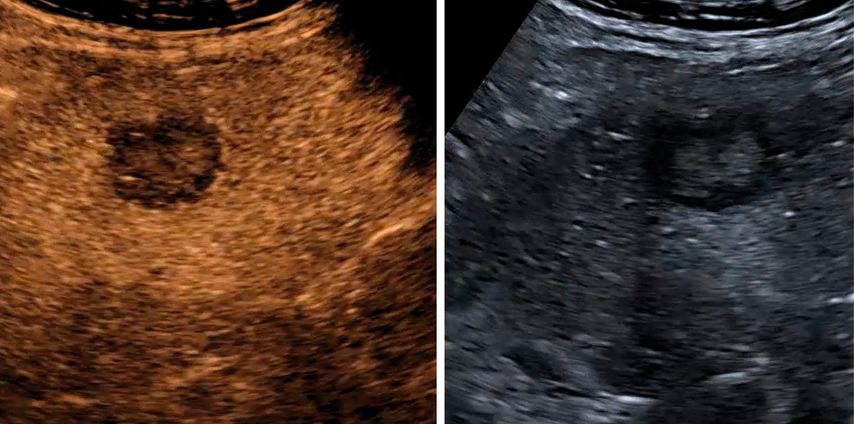

Trotz der hohen Aussagekraft moderner Ultraschallgeräte im B-Mode kann derzeit – mit Ausnahme des Screenings auf hepatozelluläre Karzinome bei chronischen Lebererkrankungen – kein generelles Leberscreening empfohlen werden.5 Die Mehrzahl fokaler Leberläsionen ist benigne, darunter fokale Steatosen, Zysten, Hämangiome oder fokale noduläre Hyperplasien (Abb.3). Maligne Raumforderungen sind in populationsbasierten Studien selten.6

Abb. 3: Darstellung einer fokalen nodulären Hyperplasie (FNH) in der arteriellen Frühphase nach Gabe von 1,2ml SonoVue® mittels CEUS (links) und in der mikrovaskulären Bildgebung (Canon®-superb «Microvascular imaging»-Modus), wo die Radspeichenstruktur besser zur Darstellung kommt

Mikrovaskuläre Bildgebung

Mit der Weiterentwicklung der Ultraschalltechnik hat sich in den letzten Jahren die mikrovaskuläre Bildgebung etabliert, welche die Darstellung kleinster Gefässe auch ohne Kontrastmittelgabe ermöglicht. Diese Verfahren nutzen spezielle Filter- und Signalverarbeitungstechniken, um langsame Blutflüsse von Gewebebewegungen zu differenzieren. Je nach Hersteller werden unterschiedliche Bezeichnungen verwendet, sie verfolgen jedoch das gemeinsame Ziel, die Beurteilung der Mikrovaskularisation zu verbessern und damit Diagnostik und Therapiekontrolle zu präzisieren.7